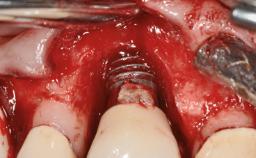

A 35-year old female patient was referred to the Department of Oral Surgery and Stomatology at the University of Bern, Switzerland, for examination of an implant site that had exhibited clinical signs of slightly delayed wound healing. In addition, the referring clinician found no evidence for a facial bone wall when she raised a flap to gain access to the implant for abutment connection. Four months earlier, she had inserted a bone-level implant in a single-tooth gap, where the lateral incisor had been extracted due to a chronic periapical lesion on the mesial aspect of the root. Implant placement was combined with simultaneous bone augmentation using deproteinized bovine bone mineral (DBBM, Bio-Oss®; Geistlich, Wolhusen, Switzerland) and a collagen membrane (Bio- Gide®; Geistlich), followed by primary wound closure. The patient also provided the postsurgical radiograph that displayed the implant with a 3.5-mm healing cap.

Bone Augmentation Horizontal|Simultaneous

Augmentation Materials Autogenous chips|Xenogenous|Membrane

Bone Volume Deficient horizontally, allowing simultaneous augumentation